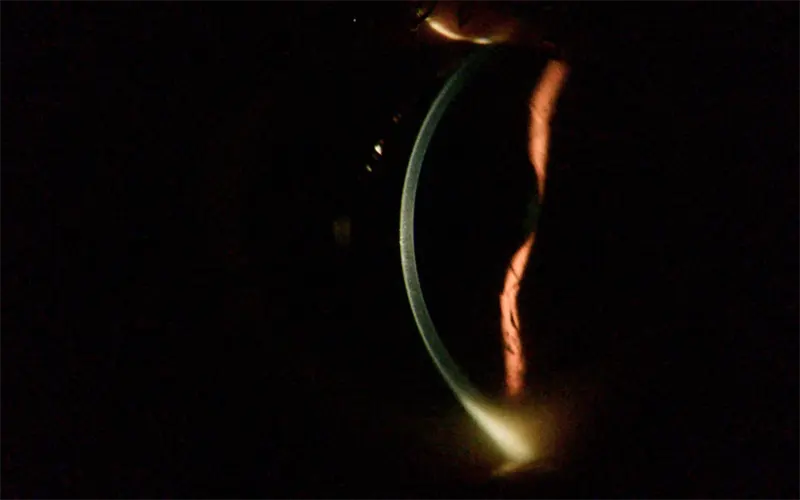

Imágenes capturadas con AIM

Estas son las imágenes capturadas en el Módulo de Imágenes Anteriores que ayudan a los médicos a realizar diagnósticos rápidos.